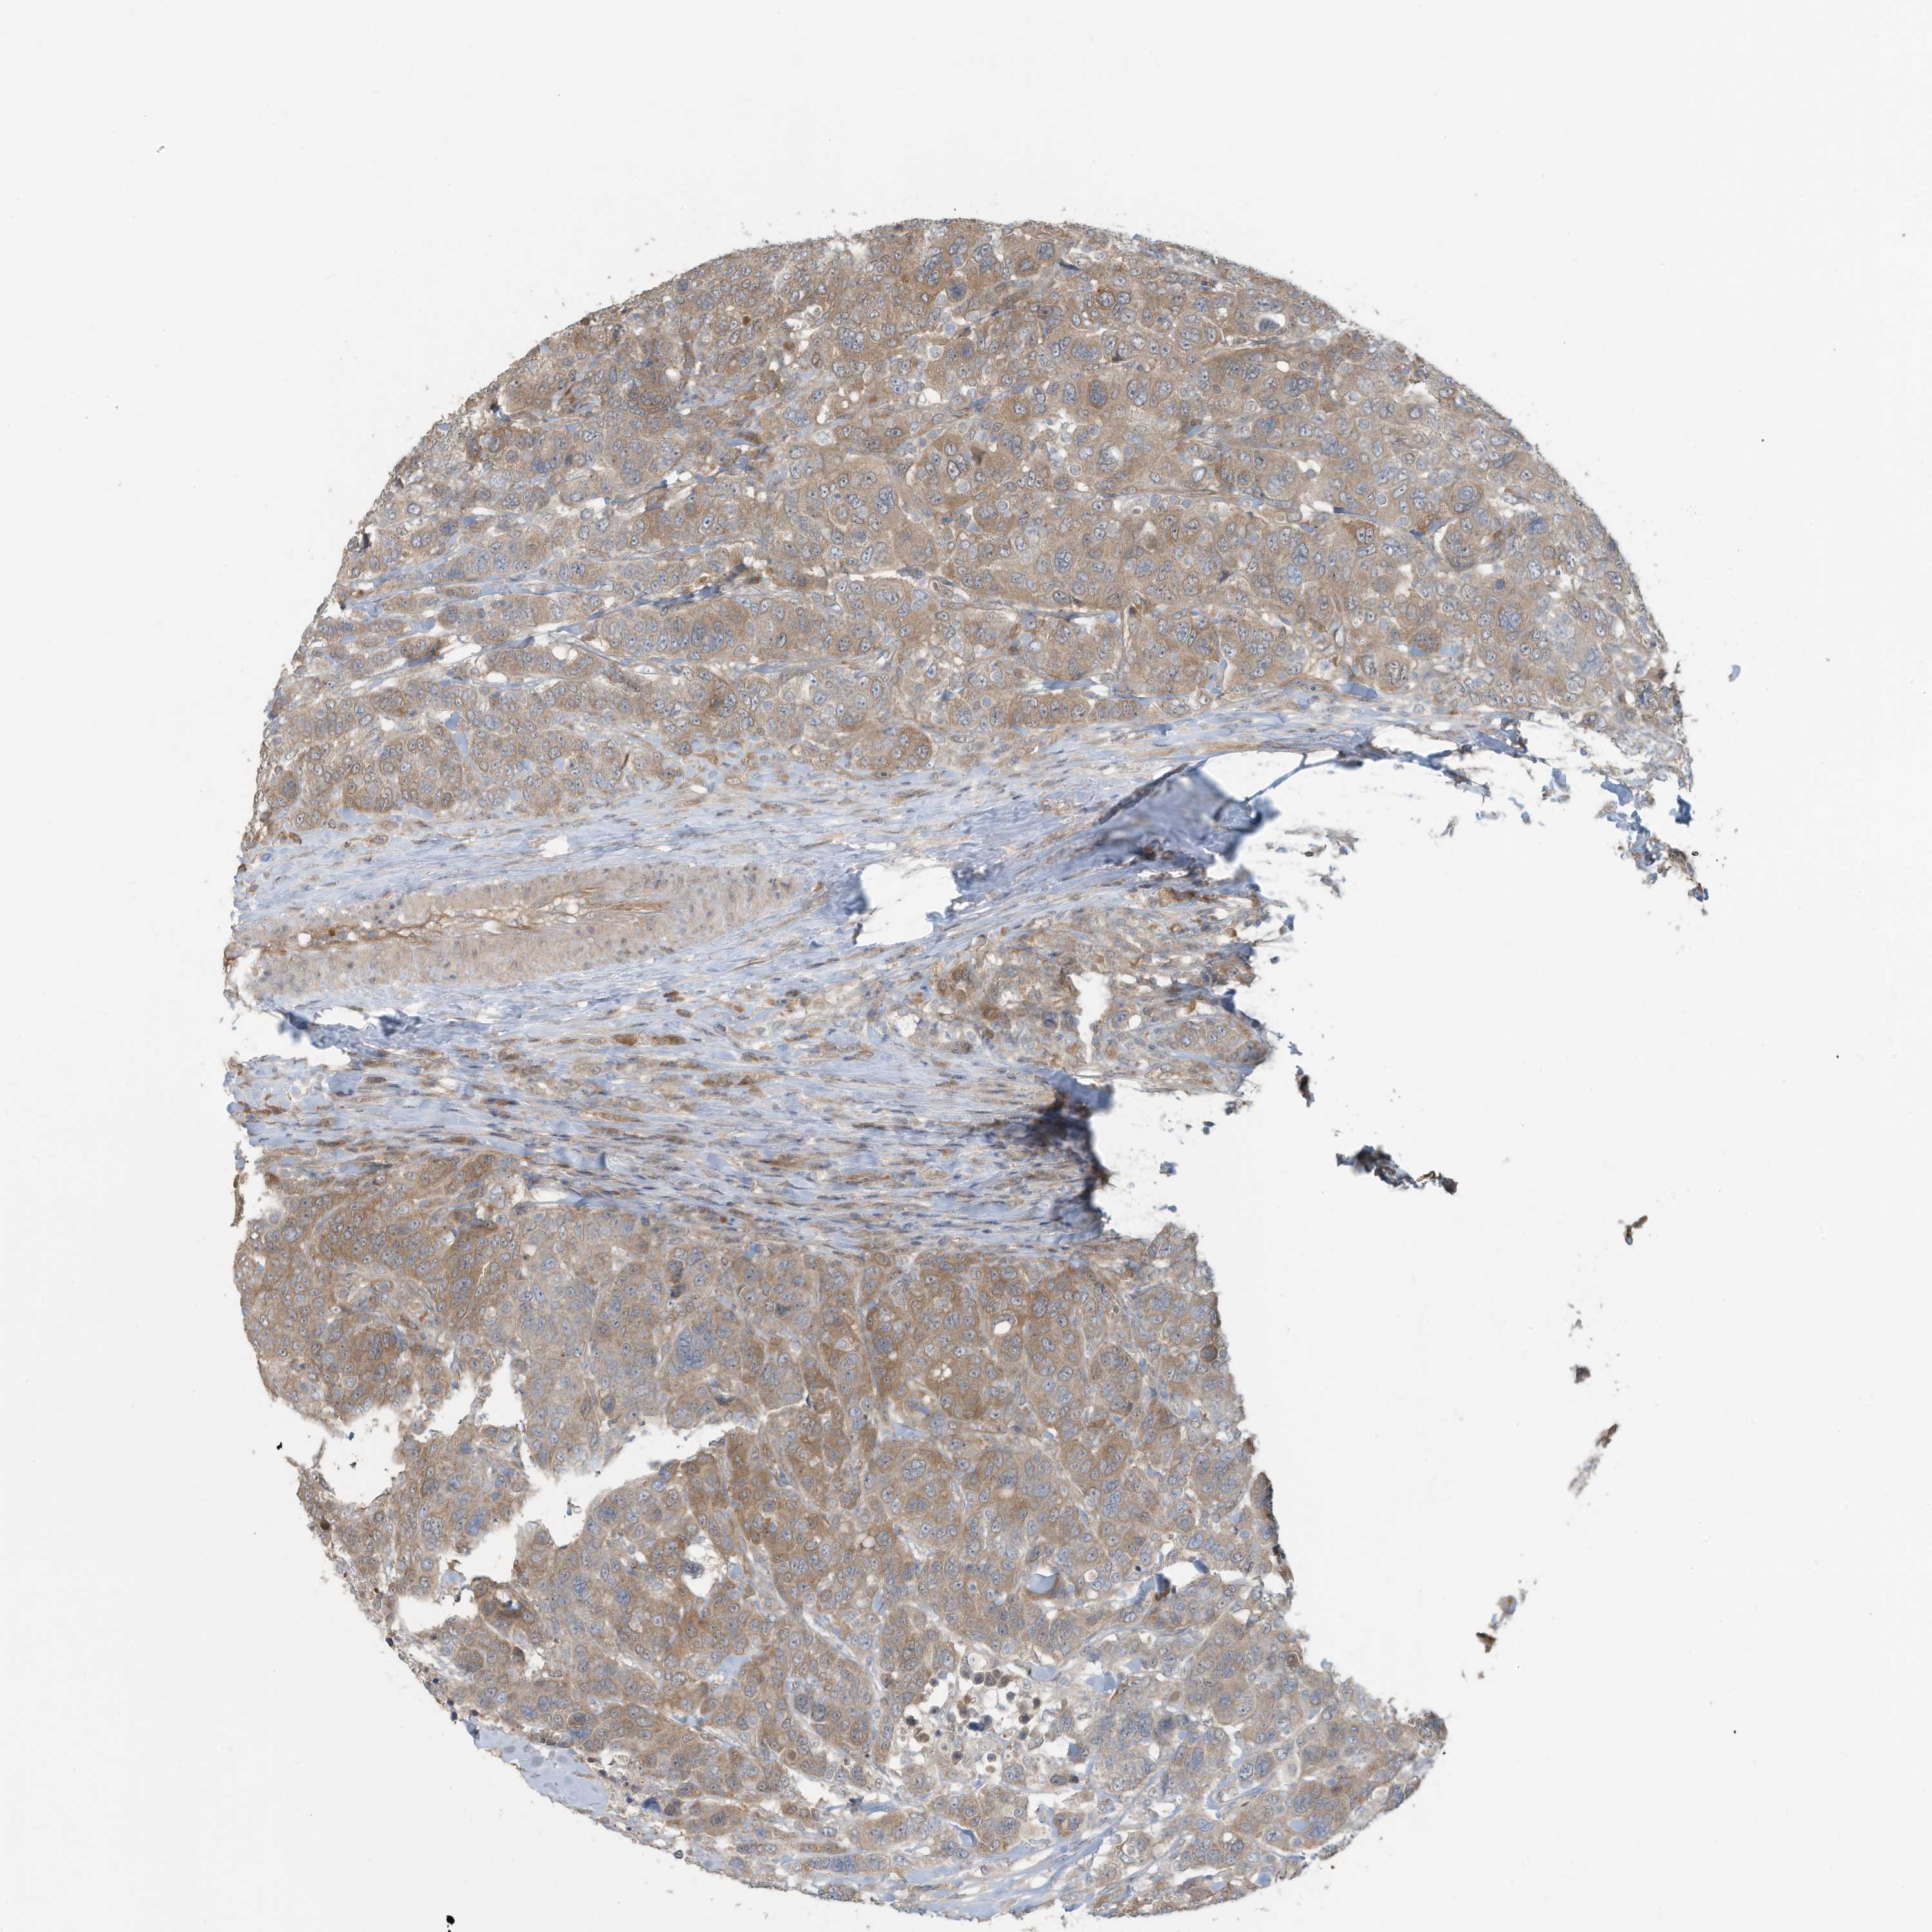

BRCA TCGA BRCA VALIDATION PROTEIN EXPRESSION

ANTIBODIES

AND

VALIDATION